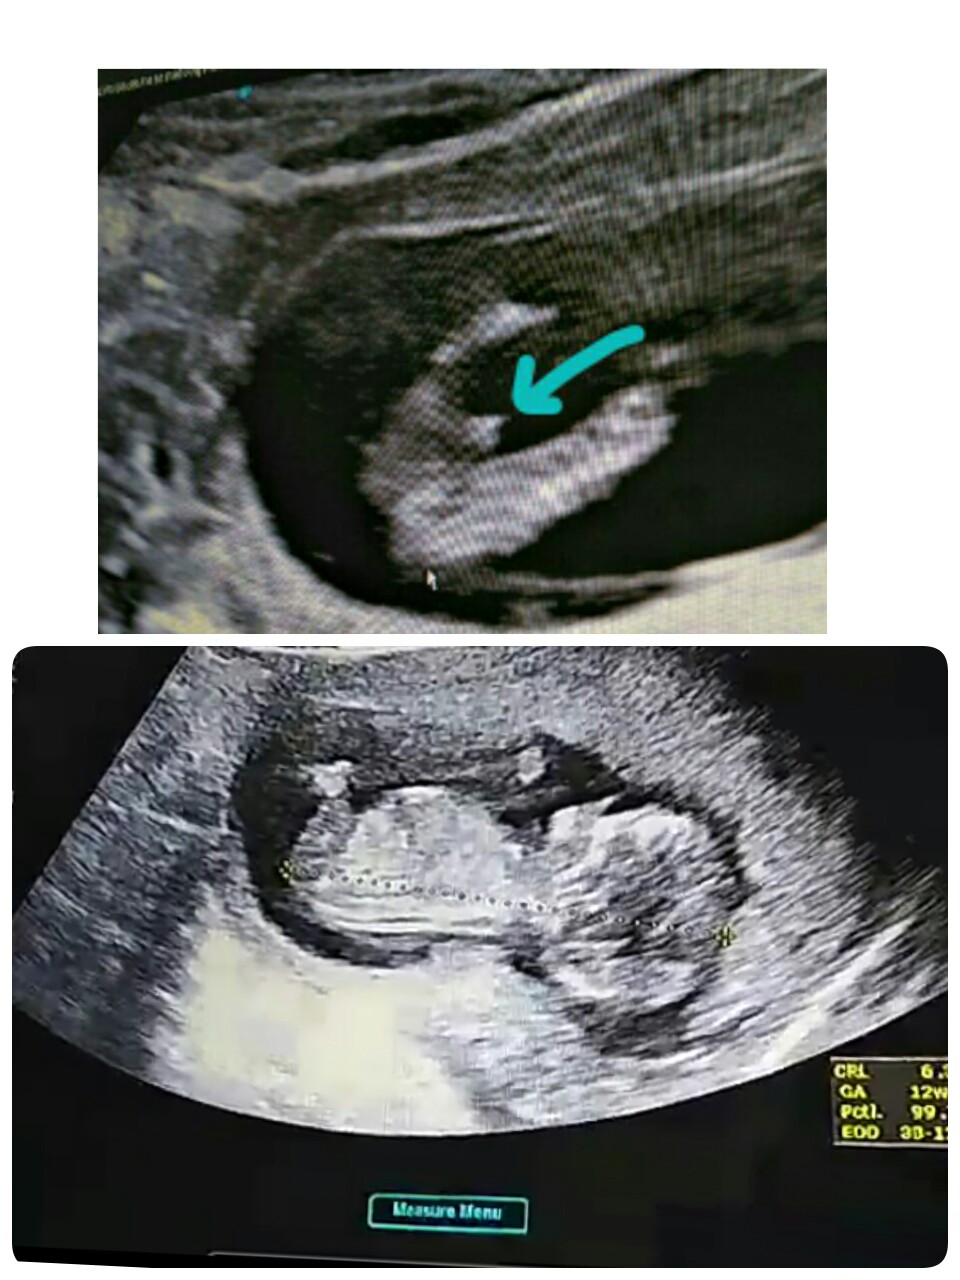

ซาวตอน4เดือนจะ5เดือนแล้วคะ